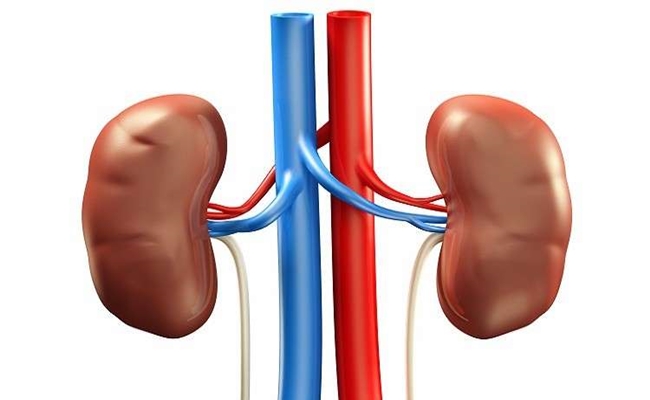

أطباء يحذرون : هذه الأطعمة تشكل حصى الكلى

وضعت مجموعة من الأطباء، لائحة بالمنتجات الغذائية التي يجب الابتعاد عنها لأنها تسبب بتشكل #الحصى في الكلى وتعطل عملها.

ونصح الباحثون بتجنب شرب القهوة (الشراب المفضل لدى مئات الملايين في العالم)، لأنها تدفع الكلى إلى العمل بأقصى طاقتها منذ الصباح، وهذا يؤدي إلى فشل في دورها الحيوي وإلى تراكم الرمل والحصى فيها، وفقاً لقناة روسيا اليوم، ويجب الابتعاد أيضا عن المشروبات التي تحتوي على الكافيين كالشاي والكوكا كولا، لأنها تؤدي إلى زيادة في مستوى الكالسيوم في البول وإلى الفشل الكلوي.

وينصح أيضا بالابتعاد عن الإكثار من تناول اللحوم الحمراء المليئة بالبروتينات والدهون، السبب الرئيسي الثاني في تشكّل الحصى، والابتعاد عن المحلّيات الاصطناعية المستخدمة في إعداد الحلويات.

وأخيرا ينصح الأطباء بالابتعاد عن الملح الذي يعطّل عمليات الهضم الحيوية في جسم الإنسان، ويؤدي إلى تشكل الرمل والحصى في الكلى.